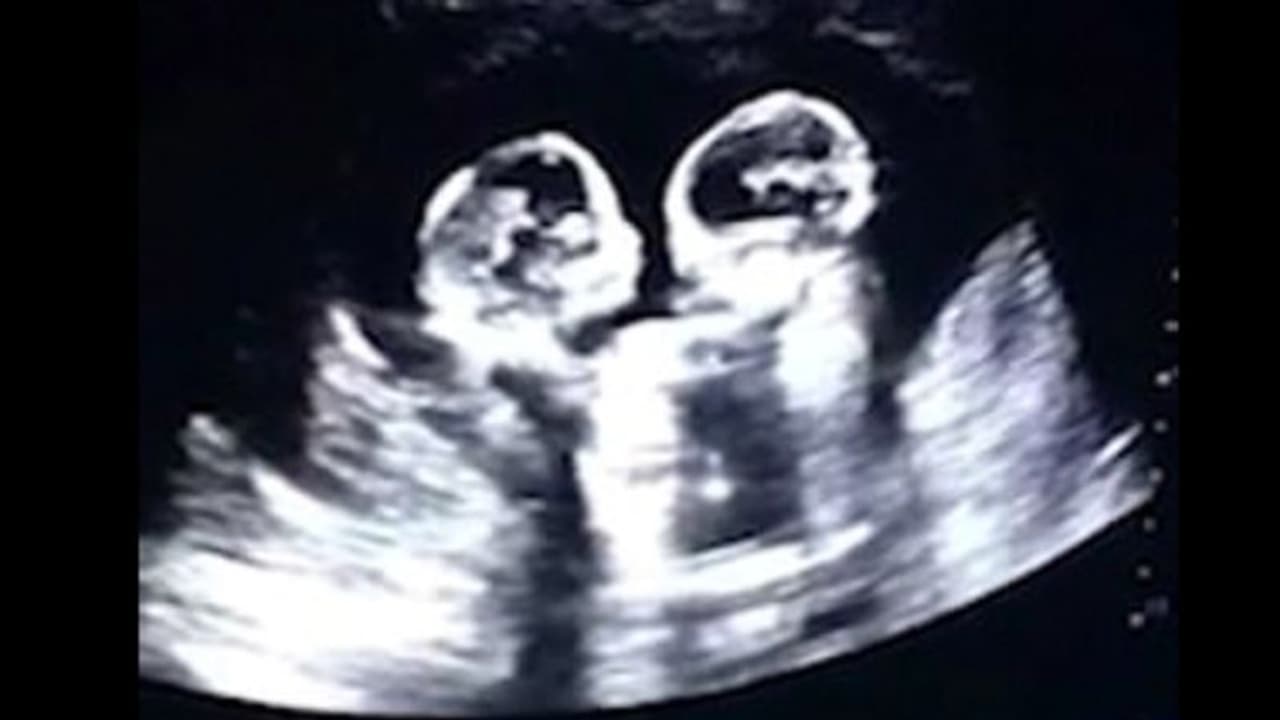

ഇരട്ടക്കുട്ടികൾ അമ്മയുടെ ഗർഭപാത്രത്തിൽ കിടന്ന് പരസ്പരം തല്ല് കൂടുന്നതാണ് സ്കാൻ ചെയ്യാൻ തുടങ്ങിയപ്പോൾ ഡോക്ടർക്ക് ആദ്യം കാണാനായത്. കുഞ്ഞുങ്ങൾ പരസ്പരം ചവിട്ടുന്നത് ഡോക്ടർ വിളിച്ച് കാണിക്കുകയാണ് ചെയ്തതെന്ന് ഭർത്താവ് താവൂ പറയുന്നു. ഗർഭപാത്രത്തിൽ കിടന്ന് ഇരട്ടക്കുട്ടികൾ പരസ്പരം തല്ല് കൂടുന്ന വീഡിയോ ഇപ്പോൾ സോഷ്യൽ മീഡിയയിൽ വെെറലായിരിക്കുകയാണ്.

അൾട്ര സൗണ്ട് സ്കാൻ ചെയ്ത് തുടങ്ങിയപ്പോൾ ഡോക്ടർ ശരിക്കുമൊന്ന് ഞെട്ടിപ്പോയി. ഇരട്ടക്കുട്ടികൾ അമ്മയുടെ ഗർഭപാത്രത്തിൽ കിടന്ന് പരസ്പരം തല്ല് കൂടുന്നതാണ് സ്കാൻ ചെയ്യാൻ തുടങ്ങിയപ്പോൾ ഡോക്ടർക്ക് ആദ്യം കാണാനായത്. നാലാം മാസത്തെ സ്കാൻ ചെയ്യുന്നതിനിടെയാണ് ഈ കാഴ്ച്ച കണ്ടത്.

കുഞ്ഞുങ്ങൾ പരസ്പരം ചവിട്ടുന്നത് ഡോക്ടർ വിളിച്ച് കാണിക്കുകയാണ് ചെയ്തതെന്ന് ഭർത്താവ് താവൂ പറയുന്നു. ഈ സംഭവം ചെെനയിലെ ചില പത്രങ്ങളിൽ വന്നിരുന്നുവെന്നും താവൂ പറഞ്ഞു. ഗർഭപാത്രത്തിൽ കിടന്ന് ഇരട്ടക്കുട്ടികൾ പരസ്പരം തല്ല് കൂടുന്ന വീഡിയോ ഇപ്പോൾ സോഷ്യൽ മീഡിയയിൽ വെെറലായിരിക്കുകയാണ്.